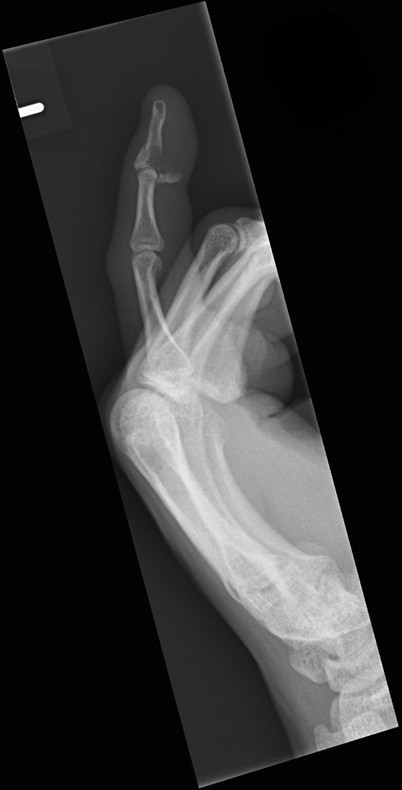

Closed rupture of extensor pollicis longus (EPL) at the wrist is the most common attrition tendon rupture. There is normally a history of distal radius fracture, often relatively undisplaced, and sometimes decades earlier. Direct repair is not possible and an extensor indicis proprius (EIP) to EPL transfer is an effective treatment.

The patient shown in Fig. 9‑1 presented to the hand trauma clinic with an inability to extend the thumb. She had been managed conservatively in cast for 8 weeks for a distal radius fracture (Fig. 9‑2). Clinical examination confirmed a ruptured EPL tendon. An EIP to EPL transfer was performed under regional anesthetic (Fig. 9‑3, Fig. 9‑4, Fig. 9‑5, Fig. 9‑6, Fig. 9‑7). The EPL which lies in the third extensor compartment is thought to undergo ischemia due to edema which consequently results in tendon necrosis and rupture.